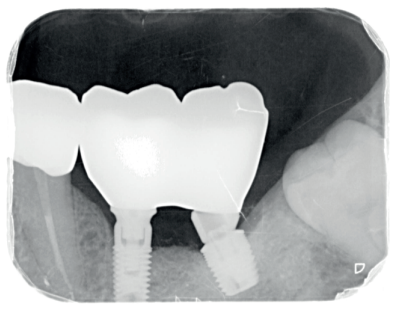

En la revisión realizada a los seis meses, el paciente ha recuperado la función y la estética y está plenamente satisfecho con el resultado (Figura 14.) La radiografía periapical de control de los implantes cargados presenta buenos niveles óseos y una completa integración del injerto de dentina (Figura 15).